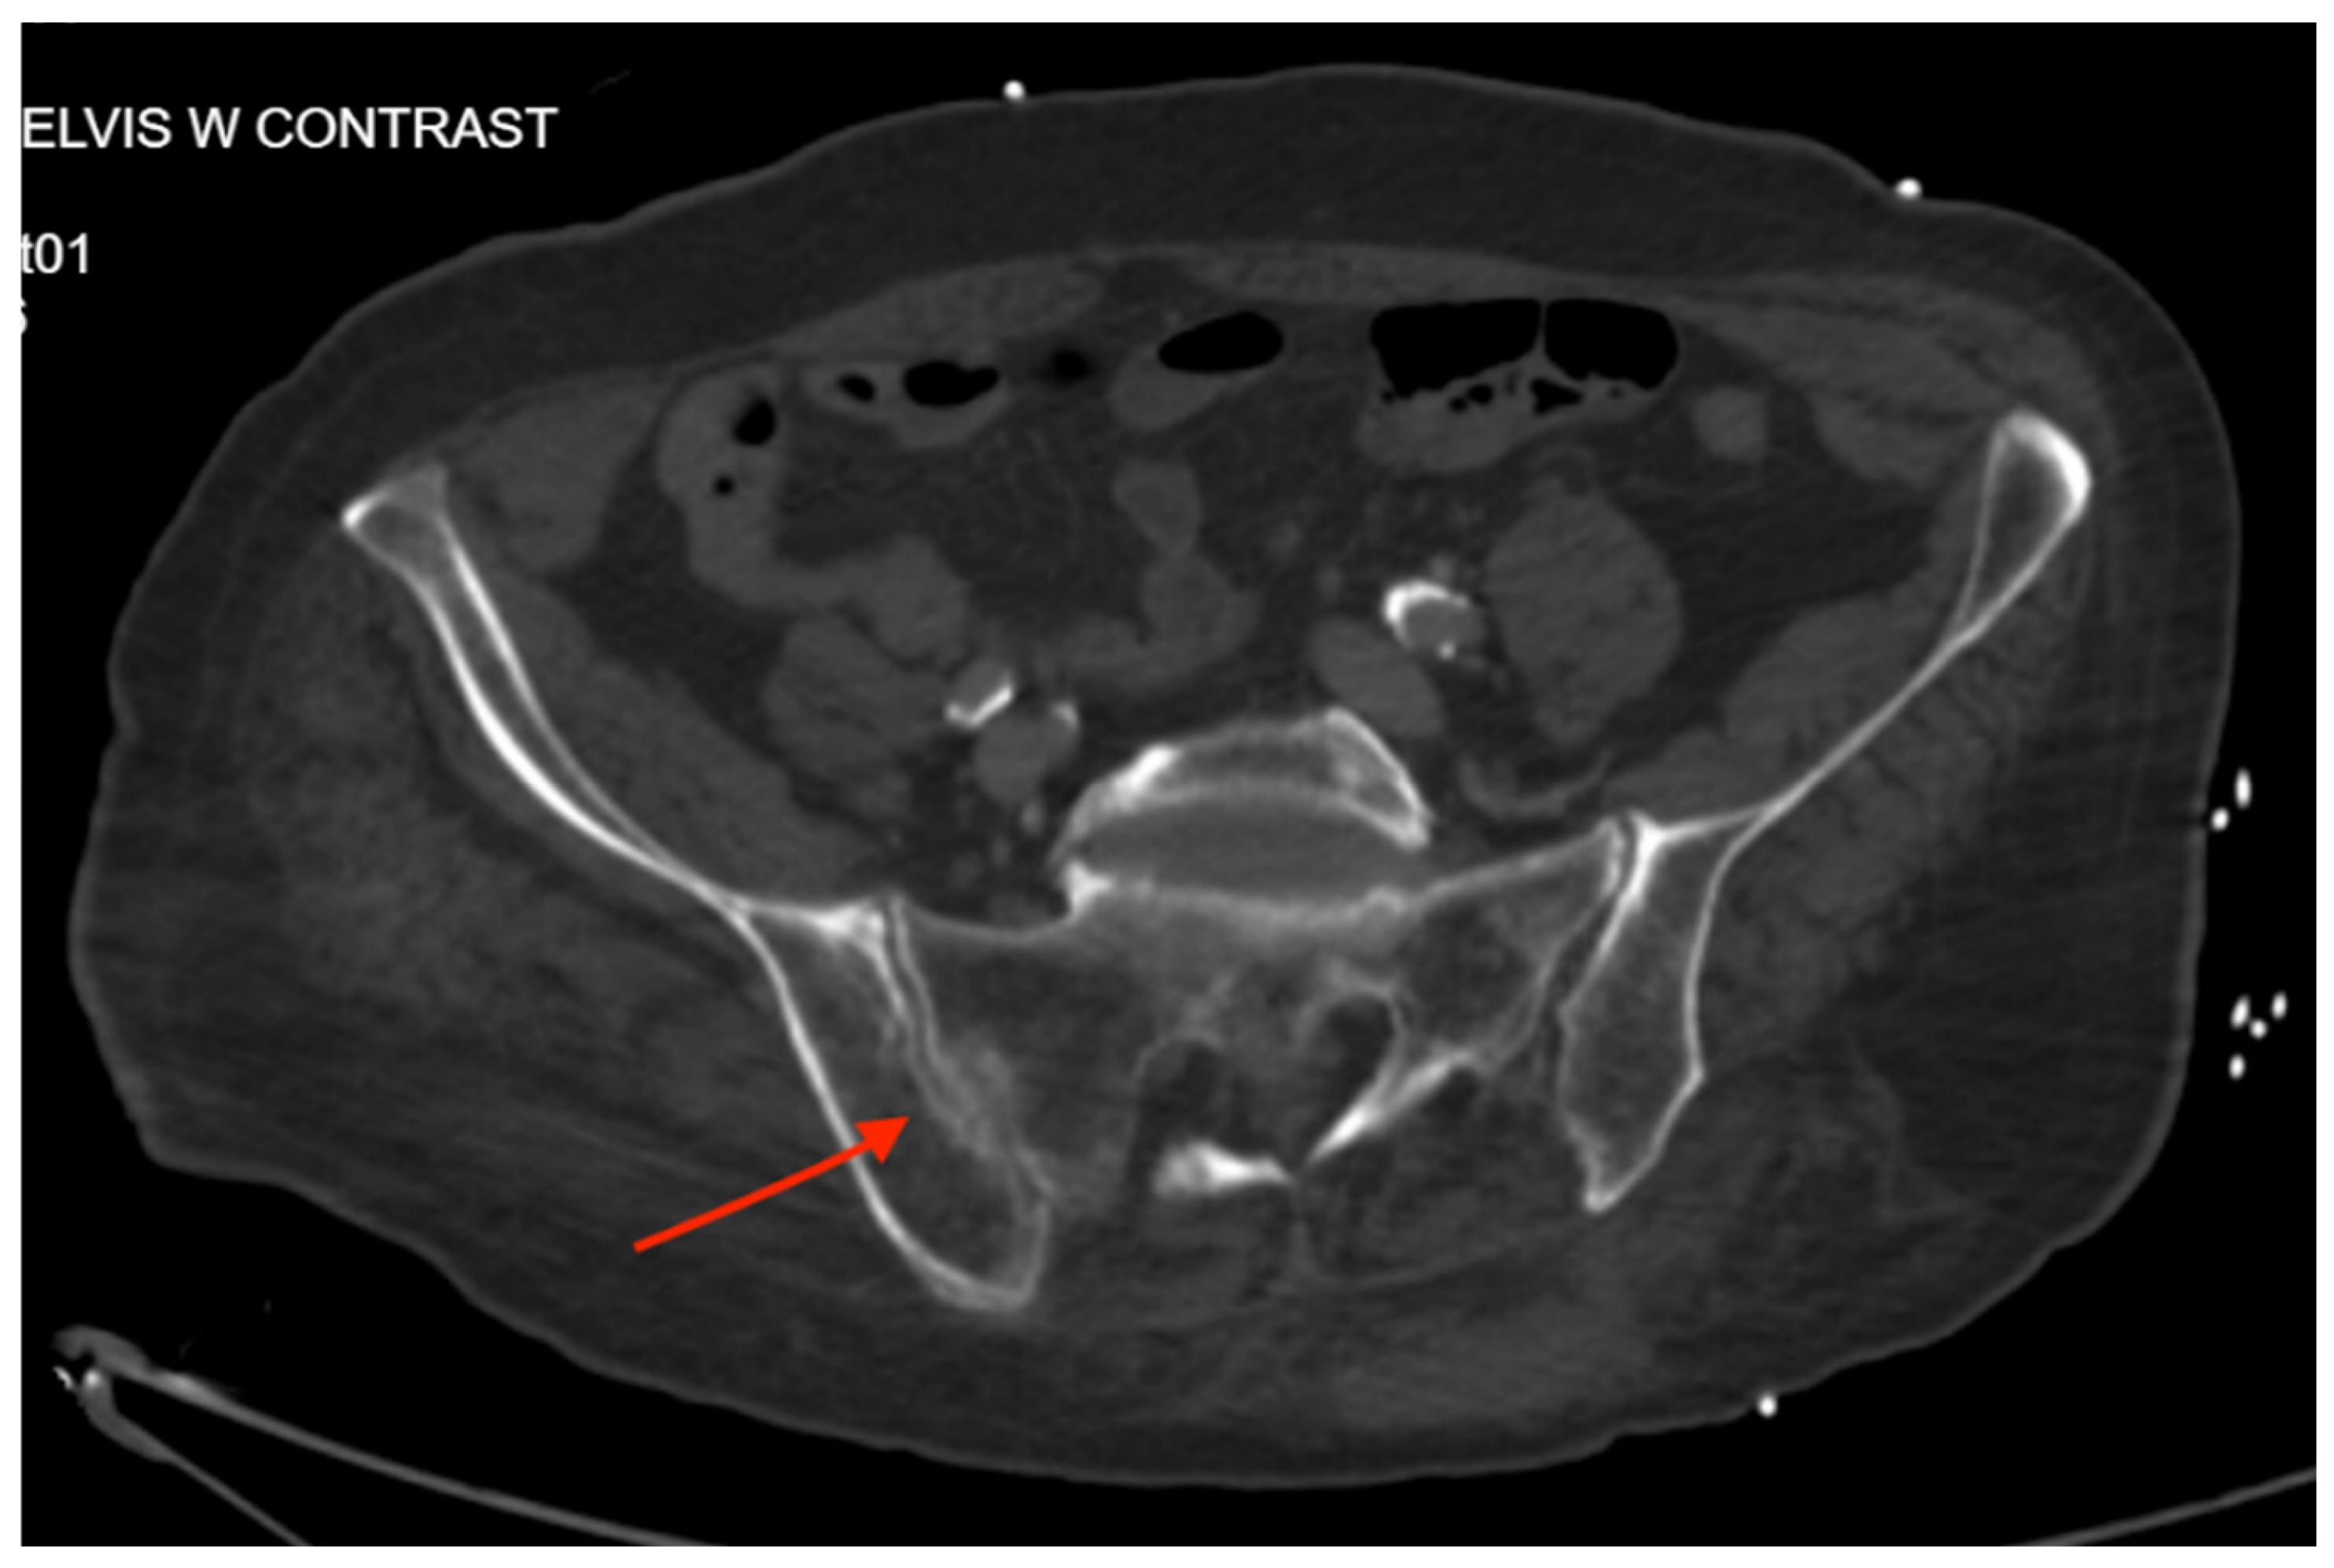

3.4.2. Imaging

Pelvic imaging performed after surgery showed a transverse S4 fracture (Figure 4). He also had multiple bilateral rib fractures, a left scapula comminuted displaced fracture, multiple cervical, thoracic, and lumbar spine fractures, and facial fractures.

Figure 4. CT abdomen/pelvis images of the described fracture in case 4. Red arrows are used to indicate the location of pelvic fractures for easier identification.